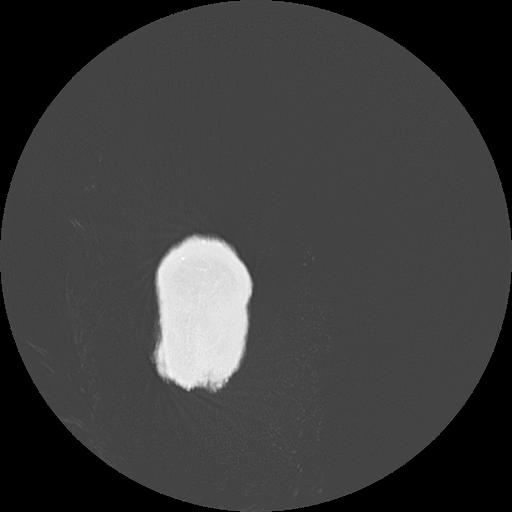

7 HUESO,,Vol,0.5,HUESO,,